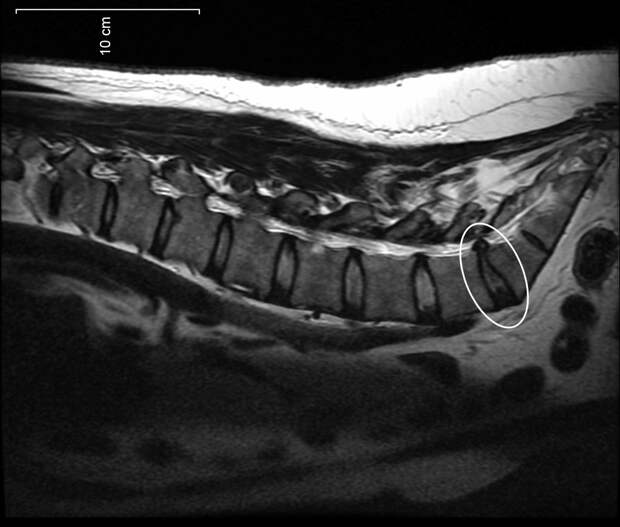

МРТ-снимок, Wikipedia

МРТ-снимок, Wikipedia

Диагностировать протрузию или грыжу позволяет МРТ. Однако перед проведением обследования при наличии болевого синдрома и других симптомов следует показаться неврологу.